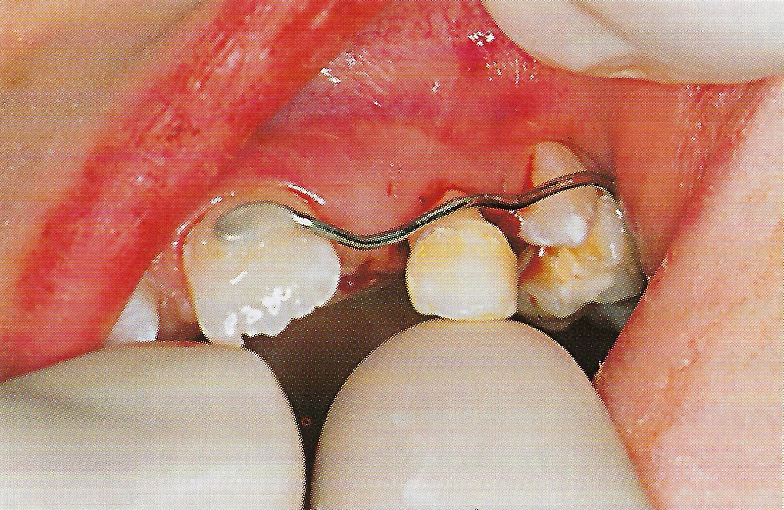

Bei der therapeutischen Ankylosierung werden zunächst die entsprechenden Milchzähne extrahiert. Da eine Ankylosierung durch eine Zerstörung des Parodontiums ausgelöst wird, muß das Desmodont mit einer Kürette entfernt werden. Obwohl unsere Patientin erst 7 Jahre alt war, konnten nach der Extraktion an beiden Milcheckzähnen, besonders an Zahn 63, bereits apikale Resorptionen festgestellt werden. Um die Zähne später sicher und vollständig replantieren zu können, mußten deshalb mehr als die üblichen 2 mm der Wurzelspitze entfernt werden. Anschließend wurden die Wurzelkanäle konventionell aufbereitet und mit einem Calciumhydoxidpräparat gefüllt (Abb. 7). Nach Entfernung des Koagulums wurden die Zähne vorsichtig replantiert und mit einem vorbereiteten Draht an den benachbarten Zähnen stabilisiert (Abb. 8). Auf den Milchmolaren wurden Aufbisse angebracht, damit die Milcheckzähne ohne störende Okklusions- und Artikulationskontakte einheilen konnten.

• Ankylose Abb.8

Abb. 8 Replantation des Zahnes 63. Der im Labor vorbereitete Stabilisierungsdraht ist bereits an den Zähnen 21 und 65 adhäsiv befestigt (Zahn 24 im Durchbruch) und wird anschließend auch mit Zahn 63 verbunden.